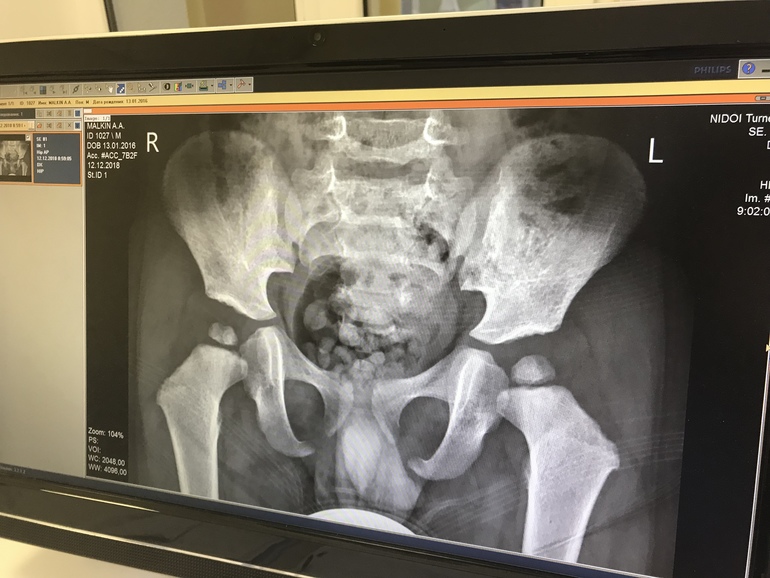

ОртопедияВ интернете представлена скупая информация по данной проблеме. Она как бы существует , но у большинства детей решается в течении первого года жизни. Мы попали с Артёмом в ту категорию, где ядра сформировались только к трём годам, то есть их не было до 1,10 месяцев. Поэтому,чтобы помочь тем мамам, которые сейчас в панике шерстят информацию про тазобедренный сустав, я ниже напишу,что и как делали мы (учитывая, что я не врач, а только рассказываю свою историю и рекомендации данные нам лечащим врачом). Если коротко, в три месяца при плановом осмотре у ребёнка выявлено отсутсвие окостенения ядер в тазобедренном суставе. Пока никакого диагноза не было поставлено, велено было ждать до 6 месяцев. В 6 месяцев уже явно вырисовывалась ассиметрия в складках, дисплазия была под вопросом (дисплазию позже сняли, так как сустав у ребёнка сформирован верно) , а так же появился диагноз «задержка развития ядер оссификации» , но велено ждать до 9 месяцев. В 9 месяцев картина полностью повторяется, на месте костной ткани до сих пор хрящи, по развитию соответсвующие ребёнку 2 месяцев. Сами понимаете нагрузка совершенно другая уже, Артём начал вставать. Мне сразу было велено не стимулировать ходьбу. К сожалению или счастью, но в 10 мес Артём стал вставать и активно пытаться ходить. К году мы пошли, сами по себе без моей какой-либо помощи. Именно в этот момент я начала хвататься за голову и искать, куда бежать. Первым местом был Нии педиатрии в спб. Нам опять в 5 раз было сделано узи (до года детей на наличии ядер можно смотреть на узи) по результатам расписано лечение: лфк, витамин д 10 капель, ауфбаукальп (пищ.добавка растительного происхождения). К году, по волею судьбы ,нам попадается хороший ортопед в поликлинике, который даёт сразу направление в институт имени Турнера в спб. На момент приёма в институте мы уже употребляли убойную дозу витамина д в размере 10 кап, прошли три курса массажа , 2 курса физио и плавали по возможности. Про массаж мамиными руками , думаю, говорить вообще не стоит. Я постоянно что-то массировала. В турнера мы попали к врачу Великановой. Врач выписала лечение в связке с педиатром, которое включало: витамин д, кальцимин, лфк+физио, а так же, внимание!, шину Виленского. Ребёнок на этот момент уже ходил, активно. На вопрос, как же нам теперь существовать, сказано было,что : « это даст вам 100% результат, привыкнете». Сутки ребёнок орал и катался по полу, я взяла на себя смелость и сняла. Одно лечим, другое калечим. Буквально сразу же я решила сменить Врача, и спустя 2 дня обратилась к Баскову (так же инст.им.Турнера). Владимир Евгеньевич сразу сказал,что шина не нужна, она ничего не даст. Нам так же расписали лечение, оно было идентично, плюсом добавилось лишь прогревание области тзс, а так же он сказал важные слова: « успокоится, проводить больше времени на солнце, ядра вырастут». Расстались мы с ним на 3 мес. Дальше при каждом приеме он делал нам рентген. К 1,4 с у нас по прежнему не было окостенения ядер, тогда врач настоятельно рекомендовал провести максимально время на солнце и море.,что мы и сделали и прожили 3 мес. По итогу, в 1,10 резко появился кариес на зубах, а вот в ядрах мы обнаружили по точке. Почему я пишу про кариес: когда у ребёнка бывают проблемы с формированием костей, то обычно и зубки отстают, так считаю ортопеды, у моего сына же Зубы появились очень рано, в год мы имели больше, чем сверстники, да и зубы сами по себе большие, хорошие. Все стоматологи отмечали, и тут кариес. Возможно, я не врач, но я предполагаю,что рост ядер как бы забрал на себя «строй.материал», и зубы «просели». Возможно, это чисто случайность, совпадение, но , однако, процесс пошёл. Врач сказал к этому моменту, что самое главное взростить ядра до 3 лет, иначе может идти деформация тзс, а так же инвалидность. Попросил не давать лишней нагрузки в виде (хоккея, футбола или иной спорт.деятельности), ну и тогда он сказал,что скорее ребёнок не сможет заниматься проф.спортом. Мы, конечно, расстроились, особенно папа-хоккеист, но здоровье главнее. Мы продолжили жить, как жили. Уже без лфк, или физио. Мы перестали принимать какие -либо препараты. Мы просто решили опять уехать на море, ребёнок получал пищу обогащенную кальцием, много плавал. В 2,11 мы на узи увидели уже два крупных ядра, которые стали активно формироваться. Врач снял диагноз!!!! Ребёнок здоров. Через год, в 3,6 лет нам рекомендован осмотр у ортопеда (в поликлинике), и можно жить обычной мальчишеской, Детской, активной жизнью. Больше бывайте на воздухе, просаливайтесь. Не переживайте. Нет людей, у которых не было бы ядер. Главное не допустить деформации тзс. Поэтому пройдя все это, все больницы, результат я увидела именно от солнца и моря. От массажа (галька, песок). От активного плавания... от сбалансированного питания! Всем Мамам